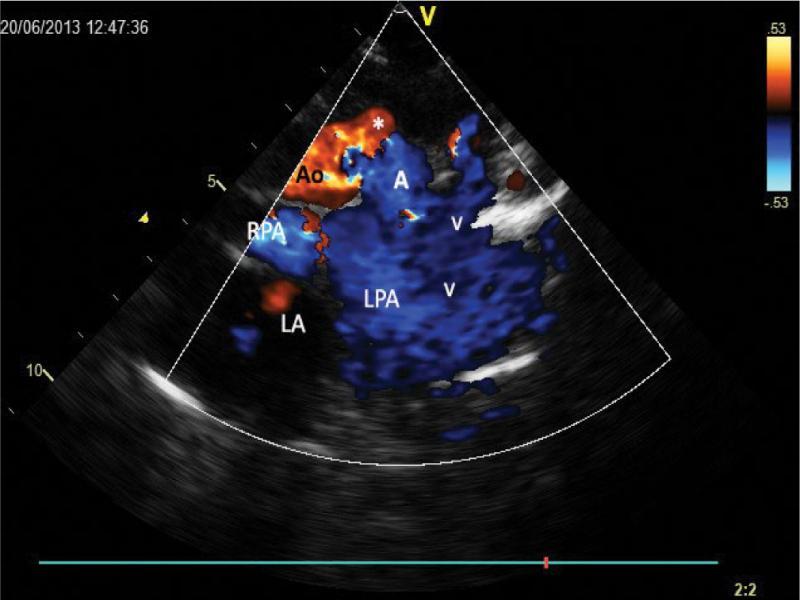

Image presented in Fig. after color removal. Without color, the vein which passes retroaortically (red dotted line) is far less clearly visualized, but its lumen can still be identified (blue dotted line)